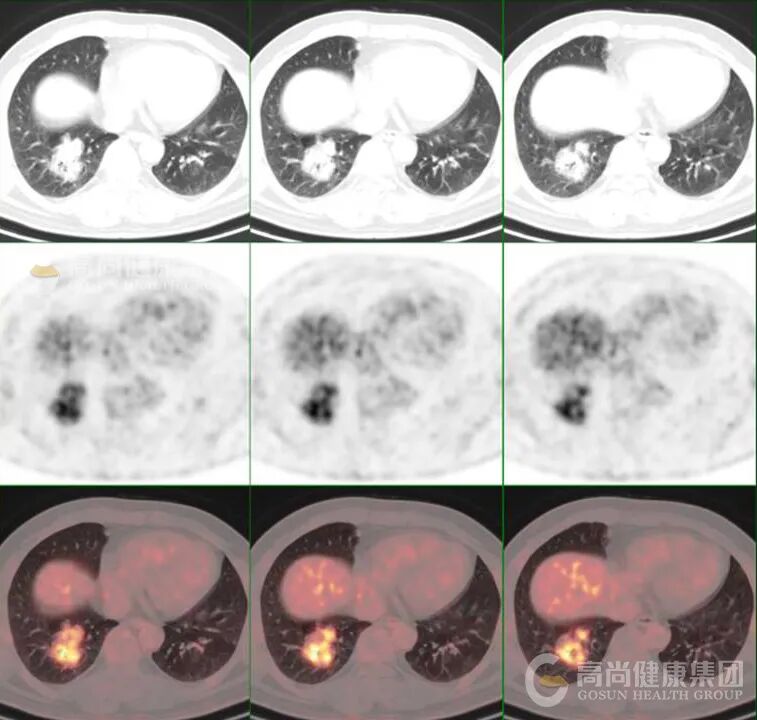

8、肺部病灶内部分高代谢灶定位于结节样稍高密度影,大多数高代谢灶以气体密度影为中心,考虑肺 Ca 并感染。

代谢活性特点:MALT 淋巴瘤作为低度恶性肿瘤,FDG 代谢常呈轻度至中度增高,SUVmax 范围多为 2.6-8.3(中位约 6.0),低于侵袭性淋巴瘤类型。

鉴别诊断价值:PET/CT 全身成像有助于区分原发性肺淋巴瘤与继发性肺部受累,且显示大多数肺部 MALT 淋巴瘤病灶存在 FDG 放射性摄取增高,但需注意与其他可导致放射性浓聚的肺部疾病(如肺癌、炎症、结核等)鉴别,需密切结合 CT 影像特征。

以下是肺部 MALT 淋巴瘤 PET/CT 典型表现的总结表格: